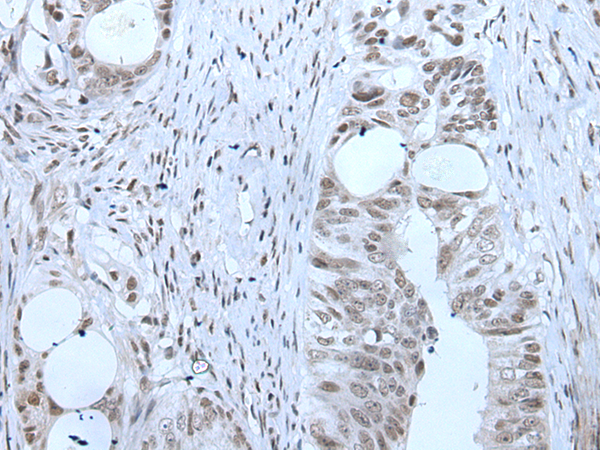

IHC positive control: |

Human esophagus cancer and human colorectal cancer |